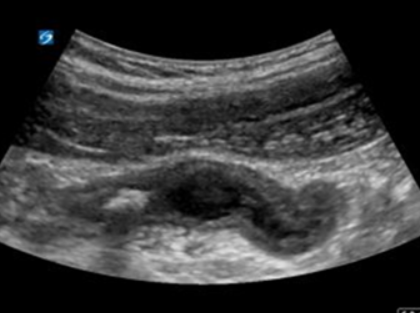

Mucocele